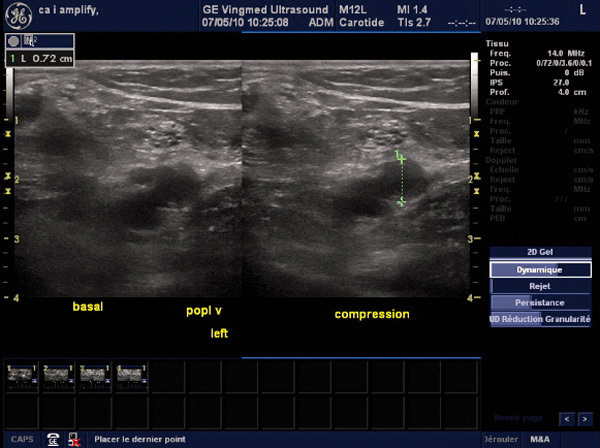

Examen échographique: la veine poplitée n'est pas dépressible.